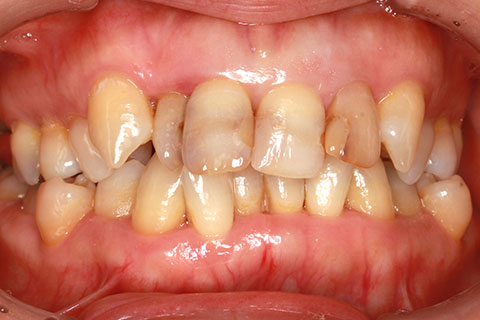

• オールセラミックの症例1

治療前

治療後

上顎前歯のデコボコと色調を改善。

年齢・性別

40歳女性

治療期間

1ヶ月

抜歯

なし

治療費

35.2万円

備考

前歯4本の変色歯及び歯列不正によるセラミック治療

治療内容

歯質を削除し、セラミック冠をセメント合着

施術の副作用(リスク)

知覚過敏、歯髄炎、荷重負担